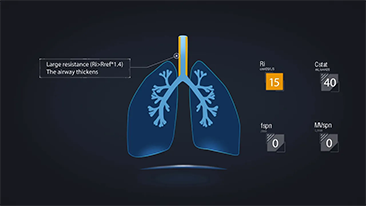

Wyb├│r odpowiedniego ustawienia respiratora do leczenia pacjent├│w z chorob? dr├│g oddechowych to bardzo wa?na kwestia. Poniewa? zadanie polegaj?ce na okre?leniu parametr├│w sprz?tu do wentylacji jest wykonywane w ca?o?ci przez lekarza, wiedza i do?wiadczenie lekarzy w wyborze tych parametr├│w ma bezpo?redni wp?yw na dok?adno?? podejmowanych decyzji. Paradygmat opieki ze wsparciem dla pacjent├│w zmieni? si? znacz?co w ci?gu ostatnich 20 lat. Na podstawie analiz potrzeb klinicznych opracowano r├│?ne tryby wentylacji i narz?dzia wspomagaj?ce podejmowanie decyzji, aby pom├│c opiekunom zwi?kszy? efektywno?? i zminimalizowa? ryzyko b??d├│w w podejmowaniu decyzji klinicznych.

??cz?c w jednym urz?dzeniu wysokoprzep?ywow? terapi? tlenow?, wentylacj? nieinwazyjn? i wentylacj? inwazyjn?, respiratory typu 3 w 1 z serii SV zapewniaj? stabilne dzia?anie, wszechstronne funkcje i ?atwo?? u?ytkowania. Unikalne funkcje ochrony p?uc i wiele narz?dzi wspomagaj?cych podejmowanie decyzji zosta?y opracowane w celu zmniejszenia ryzyka zaka?eń krzy?owych i u?atwienia opiekunom wykonywania codziennych obowi?zków.